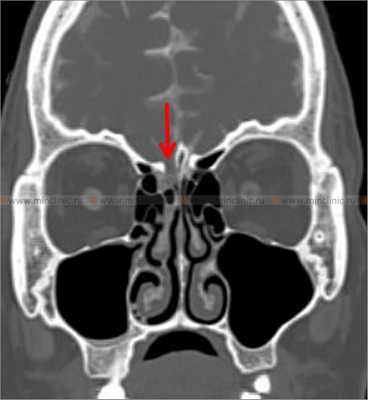

Эффективность и чувствительность КТ-цистернографии в диагностике спонтанной ликвореи достигает 71-87%. Если при КТ томографии точно определяются повреждения основания черепа, то при ясной клинической картине спонтанной ликвореи необходимость в других методах диагностики отпадает.

МРТ превосходит КТ в распознавании энцефалоцеле — грыжевое выпячивание в просвет дефекта черепа. Но МРТ хуже выявляет костные повреждения основания черепа. Эффективность и чувствительность МРТ-цистернографии при спонтанной ликворее достигает 78%. Чувствительность комбинации МРТ-методов: спин-эхо (SE) T1W1 в аксиальной и сагиттальной проекциях, SE T2W1 в аксиальной и коронарной проекциях, FLAIR составляет 100% при спонтанной ликворее.

При компьютерной томографии костей черепа с цистернографией визуализируется костный дефект правой решетчатой пластинки (указано красной стрелкой).